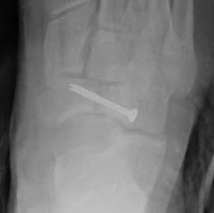

Screw technique

AO foundation navicular screw technique

Displaced stress fracture treated with single screw